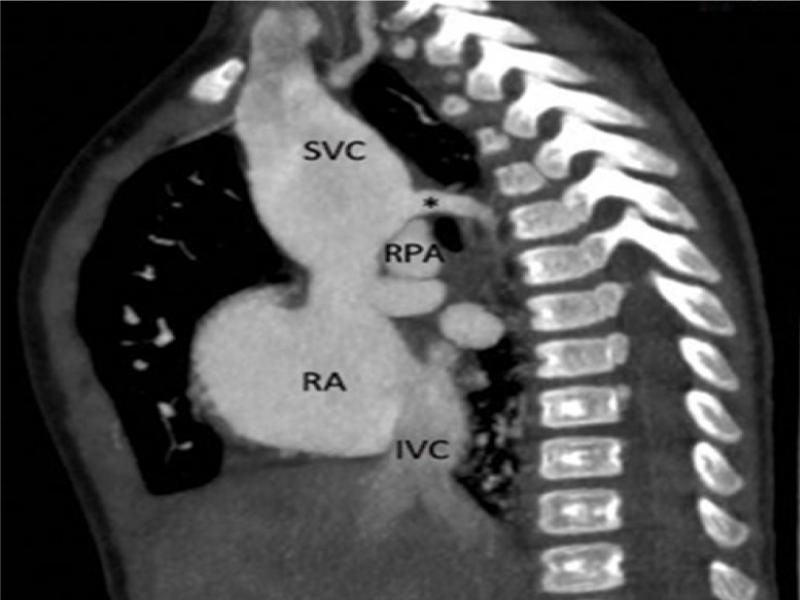

A corresponding 2D CT-angiographic view. The marked disproportion between the proximal and medial and distal part of the SVC is apparent. The prominent venous channel joining the SVC just above the crossing with RPA has typical features of azygos vein (*); runs in sagittal plane, emerges from the paravertebral space, does not receive any veins from the lungs